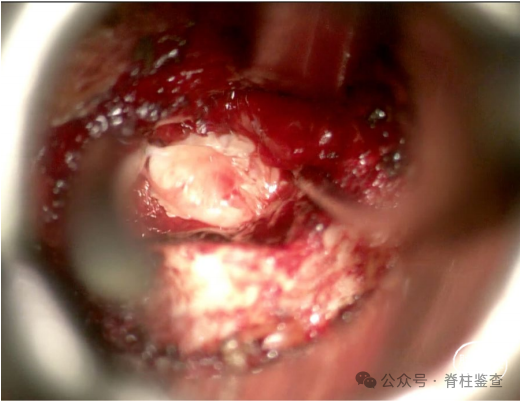

用探钩和髓核钳夹摘除椎间盘。

为确保充分减压,神经钩探查任何残余椎间盘碎片。